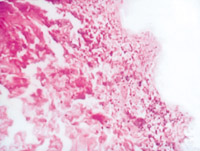

5-2-4 傷后第5天,真皮淺層組織液化性壞死、剝落  HE×100